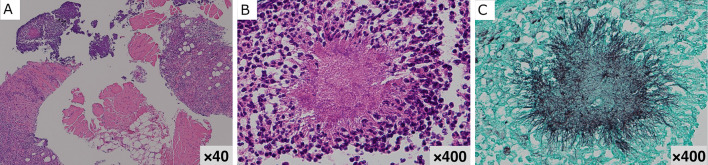

Empyema Necessitatis with Pancreatic Involvement Caused by Actinomycosis.

放线菌病所致必要脓胸伴胰腺受累。